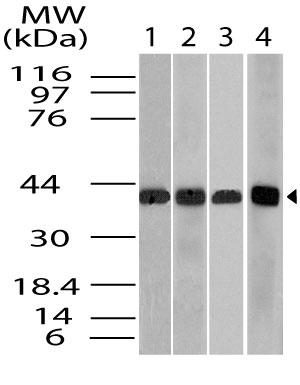

Anti-FSH Monoclonal Antibody (Clone:IHC580)

| Purification : | Protein A/G Chromatography |

Follicle-Stimulating Hormone (FSH) allows for progression of ovarian folliculogenesis, and enables Sertoli cell proliferation in the testis. Anti-FSH reacts with FSH-producing cells, therefore FSH staining is useful for classifying pituitary cancers and understanding pituitary disease.